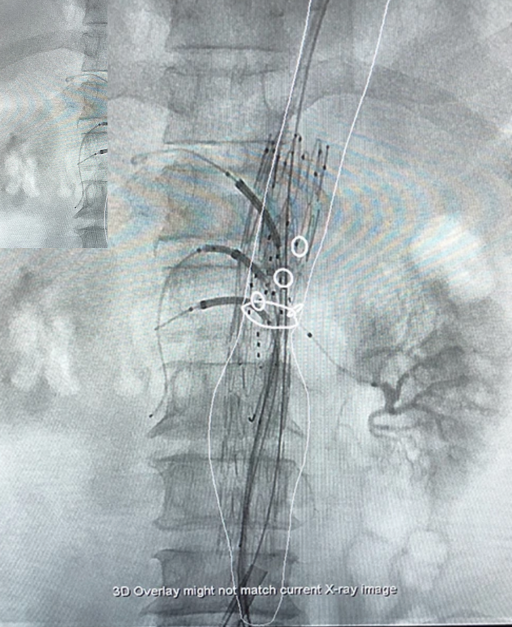

An aneurysm is the enlargement of a blood vessel to greater than 1.5 times its normal size. It is typically observed in the abdominal aorta. Despite this, about 80% of persons are asymptomatic. The remaining patients may develop abdominal pain and aeteries wall ruptures. Without prompt treatment, an aneurysm can be fatal. This problem may be treated with open surgical repair or endoscopic surgery (EVAR).

PAD is typically caused by high calcium accumulation in the arteries. The symptoms range from discomfort in the legs when walking (claudication) to leg pain while sleeping (rest pain). In certain extreme situations, leg ulcers are seen. Diabetes was discovered to increase blood clots in an artery. The treatment options include bypass surgery, balloon angioplasty, and endovascular therapy.

Patients with renal failure require vascular access to transport blood to the dialysis machine via soft tubes. The duties of vascular surgeons include the insertion of double lumen catheters, tunnel-cuff catheters, arteriovenous fistula formation, and kidney transplants.